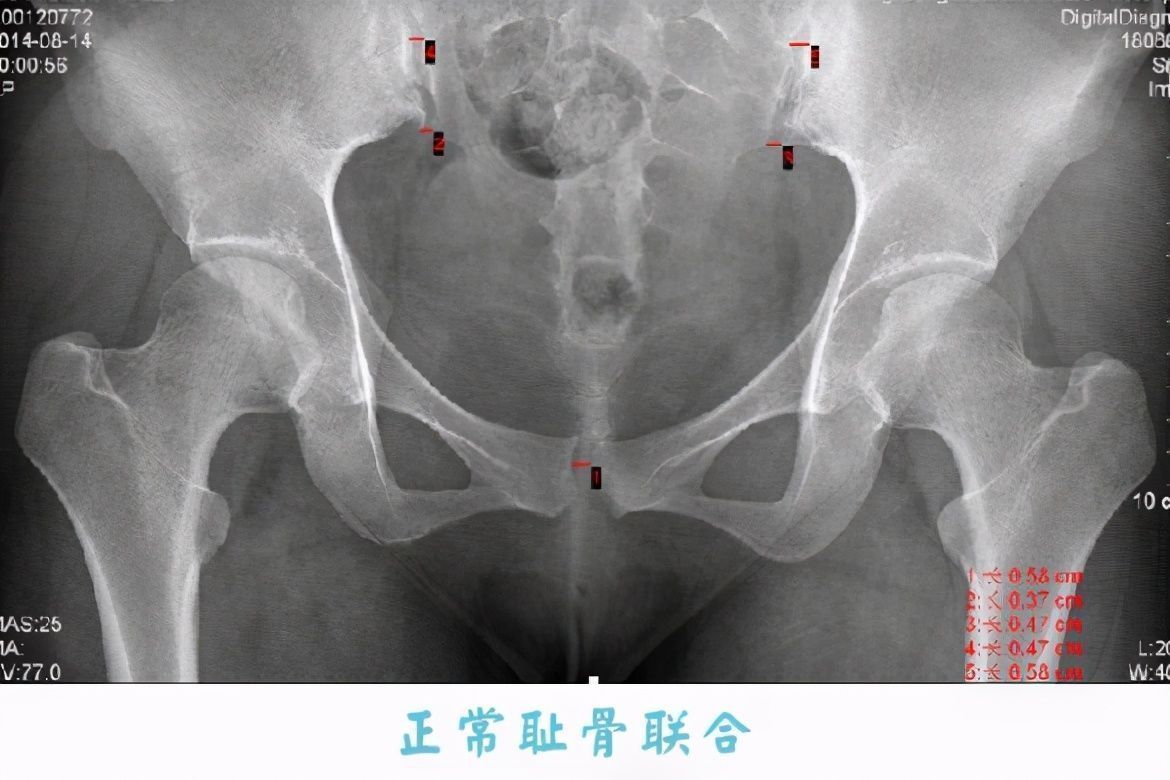

我们先来看一组对比图:

文章插图

从这张图上可以看出,正常的耻骨几乎是连接在一起的,而孕晚期耻骨联合处会出现分离的现象,正如你说看到的,有两块骨头在分离。

一般来说,孕晚期两块耻骨会分离到0.3-0.4厘米,而耻骨分离的时候会刺激到痛觉神经,所以就产生了疼痛。当然耻骨分离也是有原因的,这是为了宝妈能更容易分娩。我当初耻骨痛的时候,婆婆就在一旁说,越痛越好生产。虽然耻骨疼痛的程度跟生产之间没有必然联系,但是耻骨分离的确是为了让孕妈更好分娩。